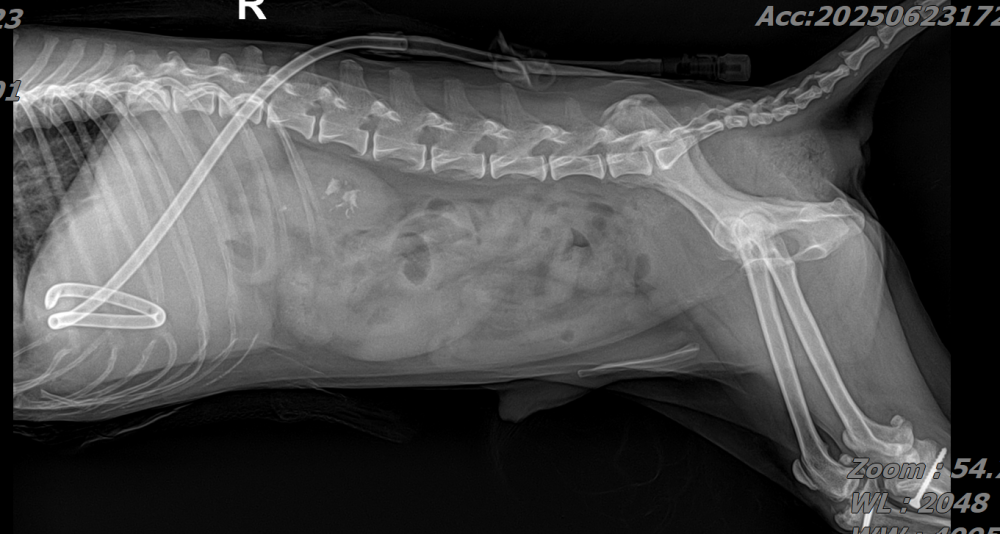

16세, 4kg의 Pompitz 수컷 환자가 식욕부진과 발열, 장염(설사)을 주소로 내원하였습니다.

해당 환자는 과거부터 반복적인 췌장염 병력이 있었던 환자로, 내원 당시 혈액검사에서는 현저한 백혈구 증가와 함께 CRP 상승, 그리고 cPL 증가가 확인되어 전신적인 염증 반응과 췌장 활성화 상태가 동반된 것으로 판단되었습니다.

복부초음파상에서도 마찬가지로 불균질한 고에코성의 췌장 실질, 주변 복막염이 관찰되었습니다. 추가로, 간에 Cystic한 mass가 관찰되었습니다.